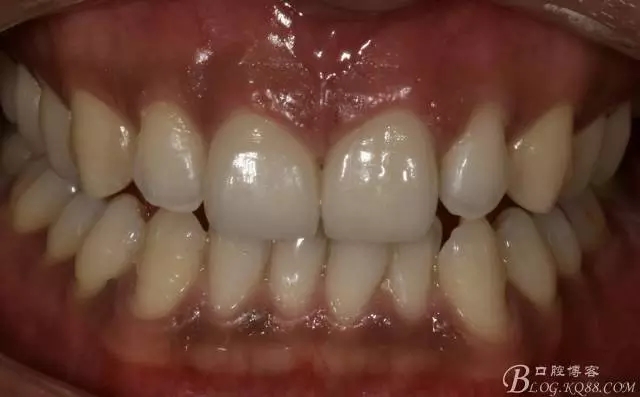

一周后復(fù)診照

舌側(cè)照